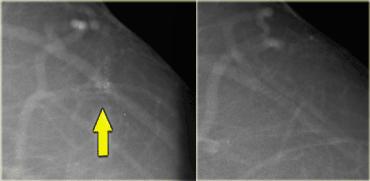

Đây là một ví dụ khác về dấu hiệu hình xăm.

Trước tiên hãy chú ý rằng có một số vôi hóa rõ ràng nằm trong da (mũi tên).

Cụm vôi hóa trên tư thế MLO có cấu hình hoàn toàn giống với cụm trên tư thế CC (hình tiếp theo).

Trên tư thế CC, cấu hình của các vi vôi hóa hoàn toàn giống nhau.

Nếu các vôi hóa này nằm ở trung tâm vú, chúng phải có cấu hình khác nhau vì góc chiếu khác nhau.

Chỉ khi vôi hóa nằm trong da thì cấu hình của chúng mới giữ nguyên.